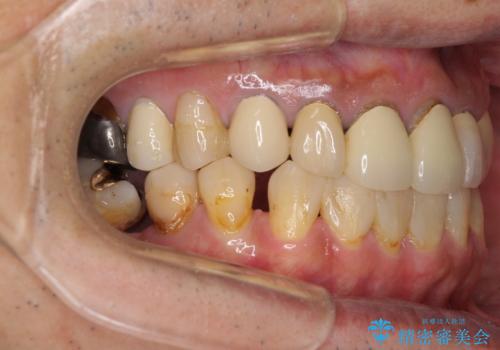

- 抜歯した歯や抜歯が必要と思われる歯を放置したため、奥歯に不快を感じているとのことで来院された患者様です。

右下は奥歯が抜歯したスペースを塞いでしまい、左下はブリッジの支台歯の1つが破折している状態でした。

また、下顎前歯にはスペースがあり、コンポジットレジンでスペースを閉じている状態だったので、前歯のスペースを解消しつつ、奥歯にスペースを獲得するよう矯正治療を行うこととしました。